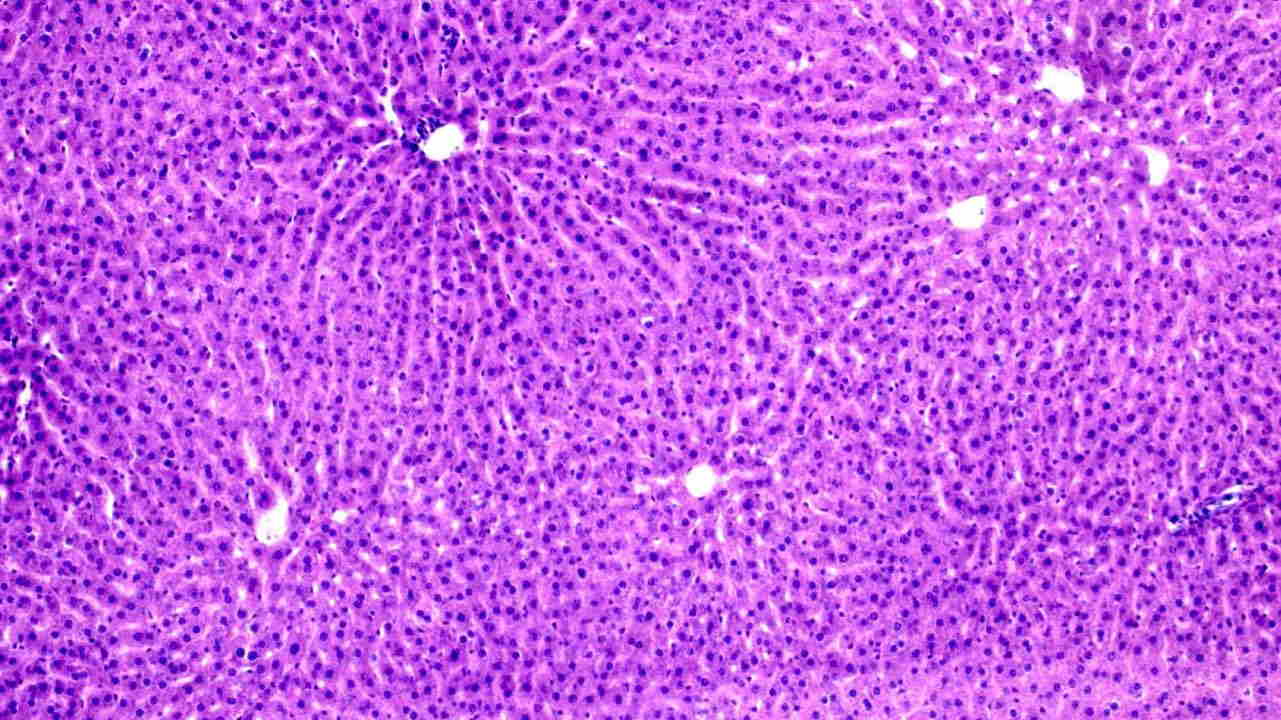

Liver Cell Isolation

Liver Cell Transplantation